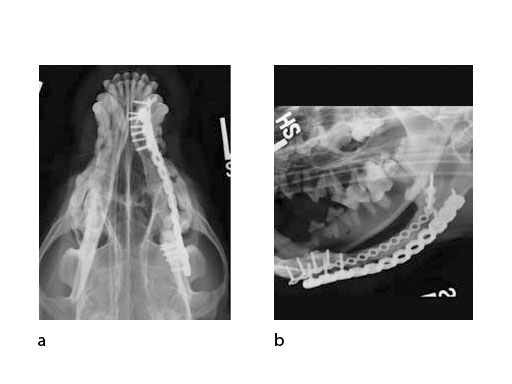

A block of compressive resistant matrix (CRM) was cut to fill this bone void, which was soaked with 2 mg of rhBMP-2. Fig 4 shows an intraoperative view of the 2 plates secured to the mandible and the CRM in place within the bone defect. The soft tissues were closed routinely. Immediate postoperative x-rays show the fixation (ventrodorsal view and lateral oblique view) (Fig 5). The radiopaque CRM can be observed spanning the 5 cm defect.

Follow-up x-rays at 7 months postoperatively (ventrodorsal view and lateral oblique view) (Fig 6) show healing of the defect (and resorption of the CRM), which was documented with a Jamshidi biopsy of the center of the original gap (Fig 7). The biopsy was performed at the same time as partial plate removal (Mini Plate) due to the intraoral plate exposure.